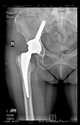

The direction of the cup stem was determined by the guide wire. The aiming device was needed to introduce this wire. After removing the aiming device, the next step was the drilling. Since a cannulated drill bit was used, the previously installed wire could guide the process. A self-positioning reaming tool was then used in the drilled channel. In the prepared cavity, the cup was fitted perfectly. Of the two stemmed cups available to us, the McMinn cup (Waldemar Link, Hamburg, Germany) had the simpler geometry and was therefore chosen. The stemmed cup was inserted according to the manufacturer’s recommendation. In the presence of a significant bone defect, a synthetic bone graft may be impacted for substitution.

The radiological examination allowed us to verify the close bone-to-implant contact and the unchanged position of the implant during follow-up.

In all the cases operated with the above-described targeting procedure, the stems of the cups remained between the cortical bone surfaces without perforation of the linea terminalis, as shown by postoperative radiographs. There were no complicated surgical situations. In 16 cases, the wound healings were uneventful, and the hips were able to bear weight again after postoperative rehabilitation.